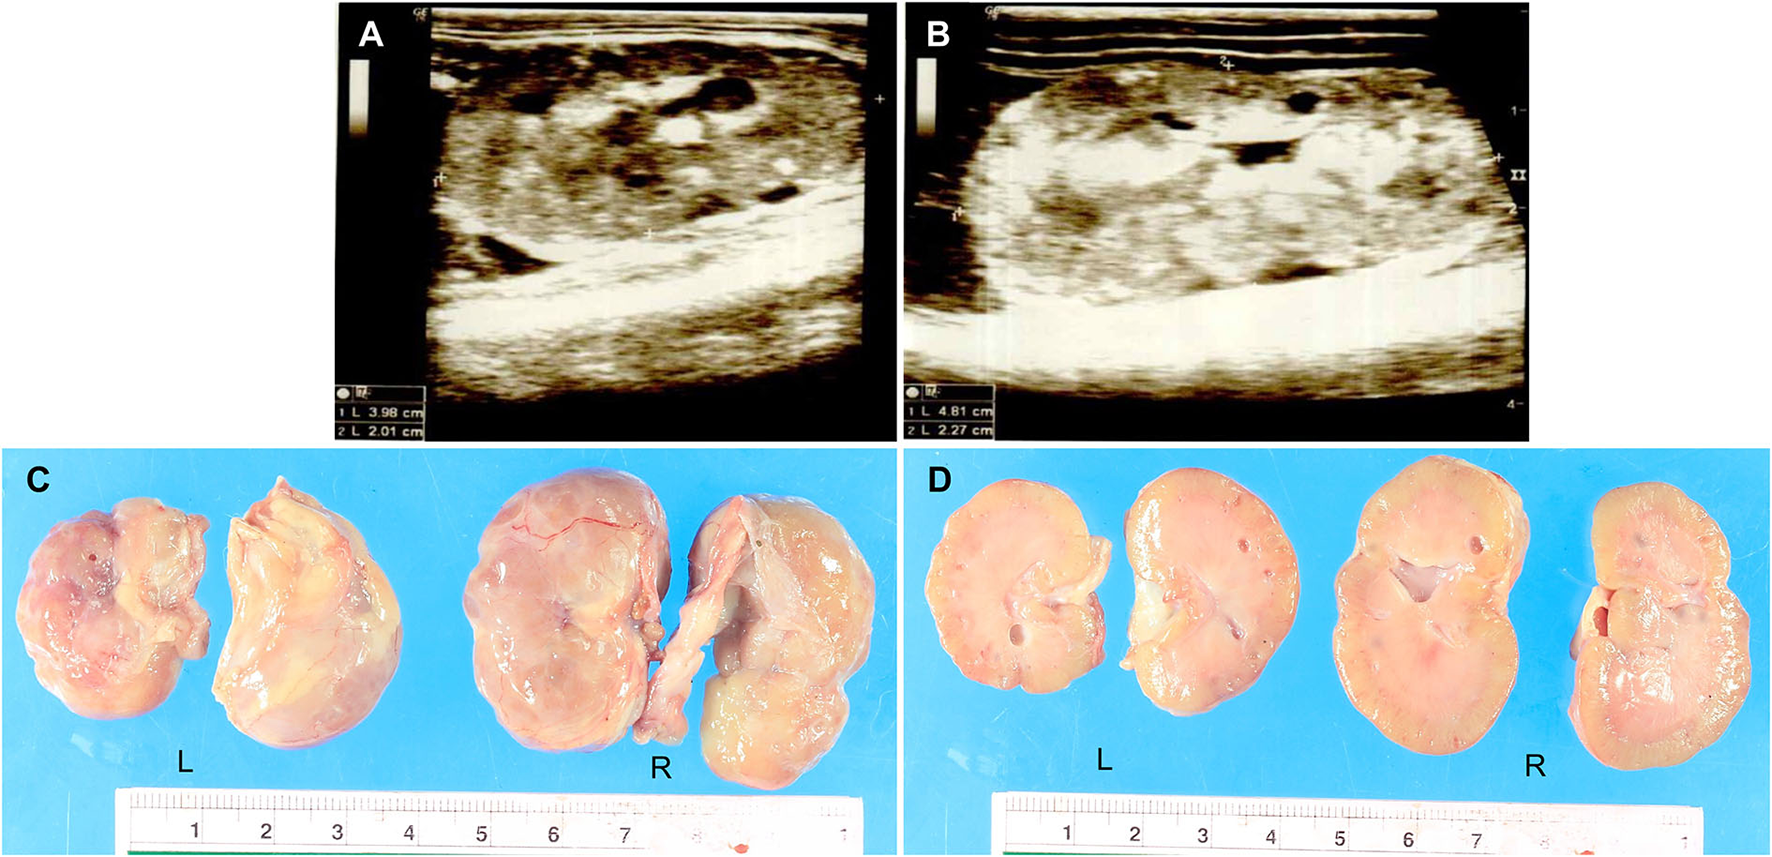

A 3-month-old, female Pembroke Welsh Corgi weighing 1 kg was referred to the Small Animal Teaching Hospital, Faculty of Veterinary Science, Chulalongkorn University, Bangkok, Thailand, to investigate and treat chronic kidney disease (CKD). The clinical information was documented from chief complaint, history taking, and physical examination. The dog was previously diagnosed with CKD and treated at a private animal hospital. Physical examination indicated a body condition score of four out of five and depression. The dog had a pink mucous membrane, normal body temperature (99oF), normal heart rate (150 bpm), and increased respiratory rate (60 bpm). Subcutaneous edema of the ventral abdomen was found. On laboratory diagnosis, the hematology and clinical chemistry revealed non-regenerative anemia, CKD stage 4 azotemia, hypoproteinaemia, hypoalbuminemia, hypercholesterolemia, hypocalcemia, and hyperphosphatemia (Supplementary Table 1). The urinalysis result showed that the urine protein/creatinine ratio was 5.77 and protein-losing nephropathy was suggested. The radiography from the thorax to the abdomen indicated peritoneal effusion and aerophagia. Besides, the abdominal ultrasonography demonstrated bilateral nephropathy with cystic formation and mineralization on both sides with ill-defined corticomedullary distinction and irregular margin (Figure 1). The size of the left and right kidneys were 3.98 × 2.01 cm (Figure 1A) and 4.81 × 2.27 cm (Figure 1B), respectively. In addition, the cytology report from the ascitic fluid revealed non-septic peritonitis. However, the medical history excluded urinary tract infections or exposure to toxic chemicals. The real-time PCR report for Leptospira species from serum was negative. The dog had been continuously monitored for the condition and received treatment for CKD.

Figure 1

(A,B) The ultrasonography report of the dysplastic kidneys. The results showed cystic formation and mineralization with ill-defined corticomedullary distinction and irregular margin. The size of the left kidney (3.98 × 2.01 cm) (A) was smaller than the right kidney (4.81 × 2.27 cm) (B). (C,D) The macroscopic findings of the dysplastic kidneys were characterized by small irregular surfaces (C). Multiple cysts showed in the renal parenchyma of both the left and right kidneys (D). L = Left kidney, R = Right kidney.

After death, a necropsy was fully performed including the gross examination and tissue sample collection from all organs for histopathology. Grossly, the dog was smaller than a normal Welsh Corgi puppy. The nutritional stage was fair. Subcutaneous edema was noticed in the abdomen. Accumulation of serosanguineous fluid in the abdominal cavity (ascites) was observed. Both kidneys were smaller and irregularly shaped; the left kidney was shrunken compared to the right kidney which was firm (Figure 1C). The renal capsule adhered to the kidney parenchyma of both kidneys and was difficult to decapsulation. The cut surface also revealed that cysts with a maximum size of 4 mm were found in the renal cortex and medulla (Figure 1D). The macroscopic findings were compatible with severe bilateral cystic hypoplasia. For other internal organs, there was no significant change that can be found in gross examination except moderate pulmonary congestion and a moderate degree of fatty hepatopathy. Tissue samples were fixed with 10% neutral buffered formalin before the routine histopathology process.